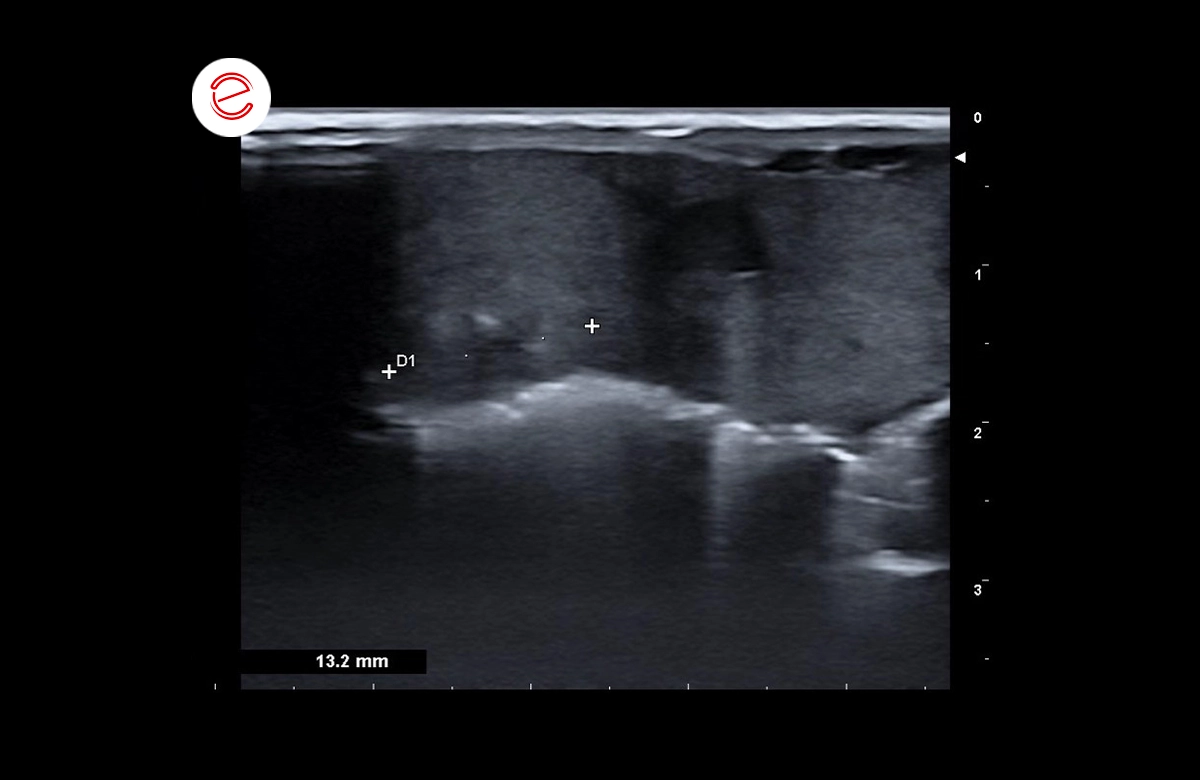

The liver is enlarged in size with rounded margins, parenchyma deformed by several oval-shaped masses, with regular contours and variable degrees of heterogeneous echostructure.

The largest mass measures approximately 3 cm in long-axis diameter.

Images were acquired using the MyLab™Omega VET system.